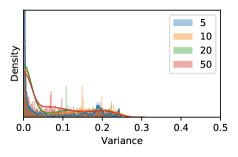

5.1 Distribution of Uncertainty Scores

Distribution of Uncertainty Scores Across Different Severity Levels As explained in Section 3, each uncertainty metric essentially defines an order/ranking among the data points. We conducted an analysis to better understand what data will be assigned high uncertainty under a particular uncertainty metric . Picking out the highest ranked data points (), we calculated the ratio of data points from each SL. Figure 4 summarizes the results as box plots for the Kaggle-DR and the Messidor-2 datasets; additional detailed statistics can be found in Table S.1 in the supplementary materials. From the plot and table, SL1 & SL2 examples account for a higher proportion among the top-ranked uncertain examples across the three ensemble methods. This finding matches our intuition that incipient disease examples (SL1 & SL2) are more likely to be considered uncertain by ensemble methods due to their ambiguity.

Comparing the three ensemble methods in Figure 4, the stacking ensemble method has the highest ratios of SL1 & SL2 data among the high-uncertainty examples it identified under both mean and var. TTA showed slightly better performance than MC-dropout but still falls behind the stacking ensemble method. Considering the fact that SL0 examples accounted for the majority of the dataset, the stacking ensemble method was much more precise (specific) in selecting truly ambiguous data points that were difficult to classify. From Figure 3, we can also see that the stacking ensemble method greatly outperformed the other two methods in finding false negatives under both mean and var uncertainty metrics.

In contrast, the MC-dropout method showed the worst overall performance among the three, as it can be seen from the high ratios of SL0 examples among the uncertain negatives in Figure 4. The histograms in Figure 2 provides another perspective to look into the phenomenon, where a decent proportion of MC-dropout model’s predictions on SL0 inputs entailed low confidence (far from 0 or 1), which from another angle explained why MC-dropout was less specific in terms of lower FNP; many no-DR inputs (i.e. SL0) were erroneously assigned high uncertainty by MC-dropout models.

As discussed in Section 5.1 and Section 5.3 in the main paper, the mean metric and the stacking ensemble will have better performance in the precision (specificity) on the ambiguous data. Here, more detailed results are shown in Figures S.3 & S.6 and Table S.1. Figures S.3 & S.4 show the histograms of the uncertainty score for Kaggle-DR and Messidor-2 datasets that are the in-distribution (i.d.) dataset in our experiment and FigureS.5 & S.6 show the histograms for ImageNet and CIFAR-10 datasets, which is the o.o.d. datasets in our experiment. Each group of histograms contains results from the three evaluated ensemble methods (stacking ensemble, MC-dropout and TTA) and the three uncertainty metrics (mean, var and kl). Additional detailed results not displayed in Figure 4 can be found in Table S.1, which shows the proportion of the data of different SLs varies across different . For comparison, we also included in Table S.1 the results from single learners, and the proportions of data of different SLs (before any selection was made).